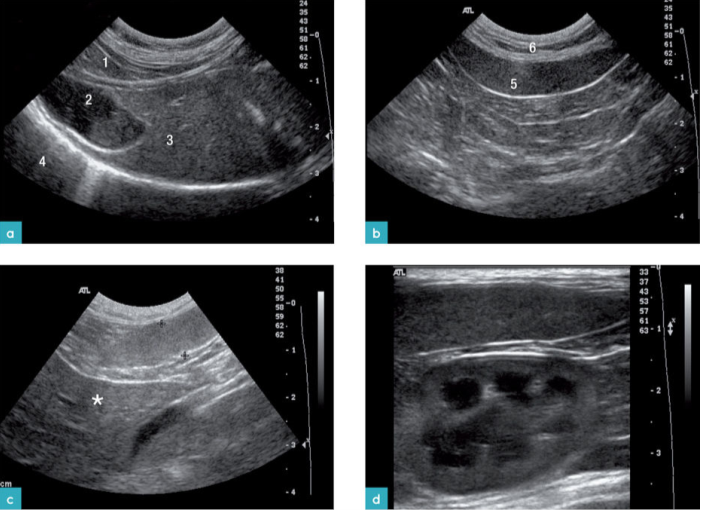

脾脏呈致密、均匀、细腻的颗粒状质地。脾脏的质地比肝脏细腻。脾脏的回声应与左肾皮质的中间部分做比较。因为超声波声束垂直于肾脏表面时,肾脏两极的声波会发生衰减,所以不应与肾脏的两极的回声做比较。有报道称脾脏的实质回声比肝、肾的回声强。然而,有些的研究表明,正常猫的肾皮质回声比脾脏的回声强,因为在猫肾脏皮质中的肾小管沉积了较多的脂肪(图5)。

在脾脏的脏器面,血管周围的脾脏实质内偶尔会发现高回声结节。这些结节与脂肪蓄积相关,被称为脂肪瘤或髓脂瘤(图6)。